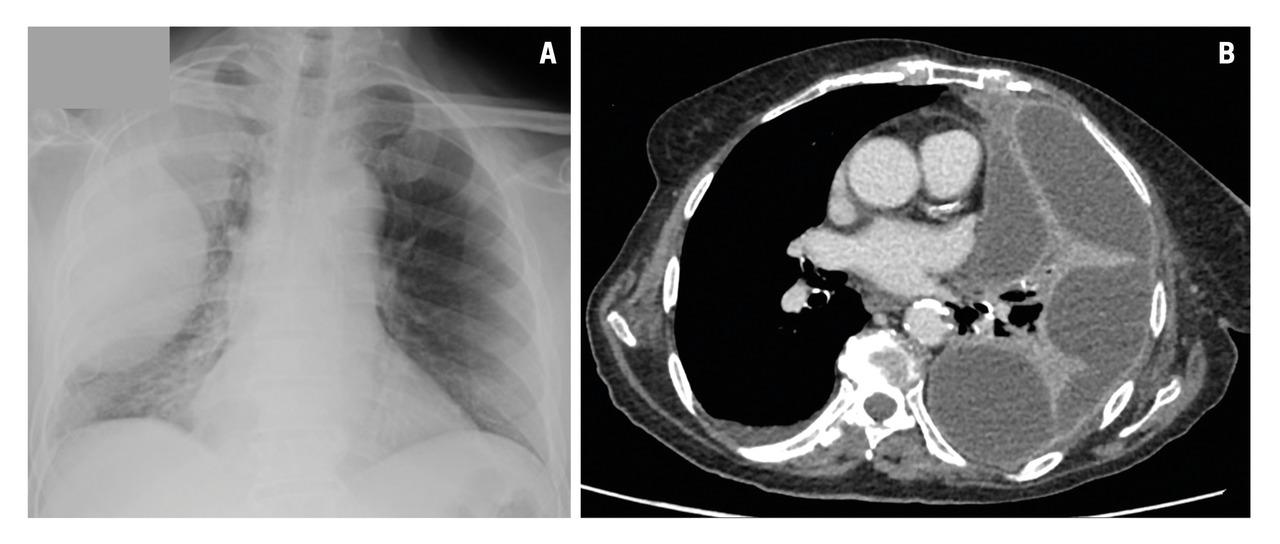

L’épanchement pleural liquidien peut être évoqué dans des circonstances particulières (tableaux 1 et 2) fondées sur la clinique, à l’occasion d’une douleur thoracique ou d’une dyspnée récente, d’un examen mettant en évidence une nette diminution, voire une abolition du murmure vésiculaire (le plus souvent en zone basale, mais parfois situé plus haut, en cas d’épanchement suspendu). Si l’échographie peut être utile, seule la radiographie thoracique permet le diagnostic : elle précise la localisation uni- ou bilatérale, basale ou enkystée, l’abondance, une compression éventuelle sur le médiastin ainsi que d’éventuelles lésions associées. Ces éléments sont fondamentaux pour éviter la réalisation d’examens inutiles et/ou potentiellement dangereux, notamment dans le cas d’un épanchement bilatéral, le plus souvent en lien avec une insuffisance cardiaque gauche. La radiographie thoracique ne permet pas toujours d’identifier une cause (aspect non spécifique), mais un épanchement suspendu ou multicloisonné (fig. 1) évoque en premier lieu une pleurésie infectieuse.

À la suite des examens de première intention, si le diagnostic reste méconnu, un scanner du thorax avec injection de produit de contraste est réalisé (fig. 2). Il permet de rechercher notamment une embolie pulmonaire, un rehaussement pleural nodulaire et une tumeur intra-thoracique.2